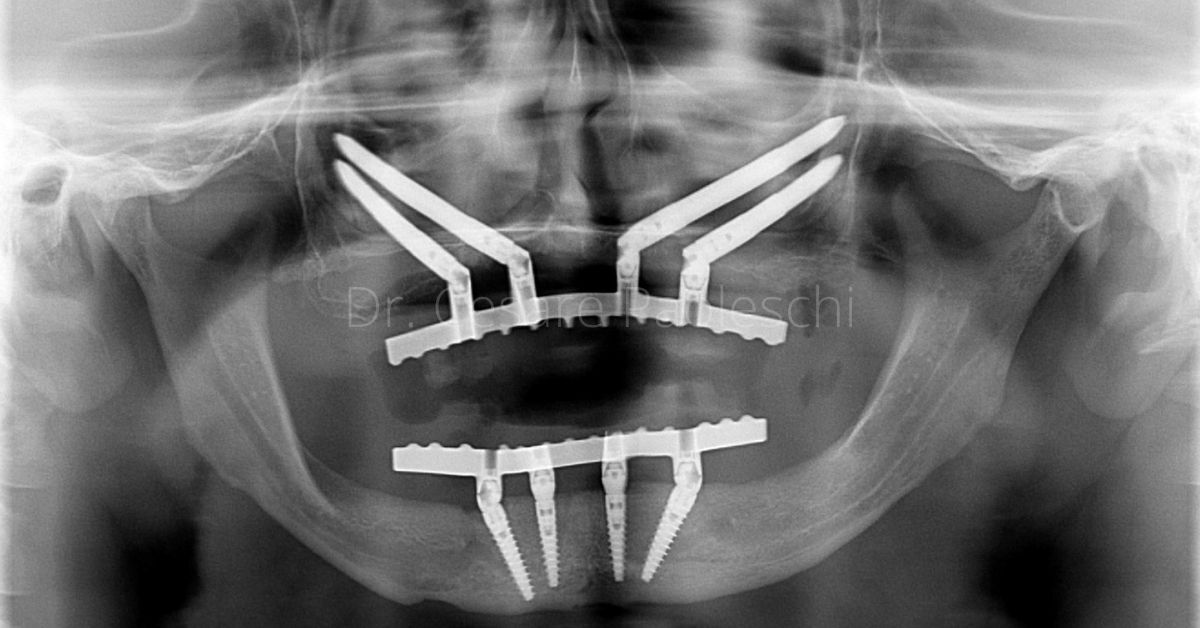

FASE 2 - Studio del repertorio radiologico (Tac – Panoramica – Radiografia) e della stereolitografia

Riabilitazione Gravi Atrofie

Da oltre 37 anni si occupa di implantologia osteointegrata e da 12 anni esegue interventi di riabilitazione mediante la tecnica degli impianti zigomatici. Nel 2025 ha eseguito oltre 350 casi di riabilitazione di gravi atrofie mediante le più sofisticate tecniche di chirurgia implantare.